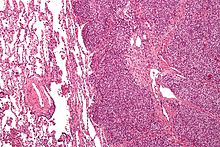

There are typically many small cells of the same size and appearance, with round nuclei.[3] Around half have extensive glycogen deposits, demonstrated with positive PAS staining.[3] Around 85% of Ewing sarcomas are positive for CD99, a cell-surface glycoprotein.[1] However, CD99 also occurs in some normal tissue and in other round cell sarcomas, as well as in lymphoblastic lymphoma and leukemia.[3] There may be keratin expression.[1]

Micrograph of metastatic Ewing sarcoma (right of image) in normal lung (left of image). PAS stain

Micrograph of a metastatic Ewing sarcoma with the characteristic cytoplasmic clearing on H&E staining, which was showing to be PAS positive